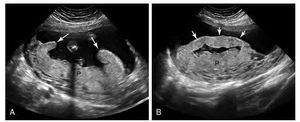

Schematic diagram comparing normal placenta (left) and circumvallate placenta (right). The membranes insert at the edge of the normal placenta, whereas they insert on the anterior surface of the circumvallate placenta, central to the placental edge. As a result, the circumvallate placenta has a raised rolled layer of thickened membranes and placental tissue resulting in a clublike appearance of the placental edge. Cireumvallate placenta. A, Longitudinal image of the uterus during late second trimester shows a posterior placenta (P) with raised edges in a clublike configuration (arrows) due to circumvallate placenta. Oblique image of the same placenta (P) as in image A depicts the raised edge of the placenta as a linear band of tissue (arroes) that resembles a uterine synechia.